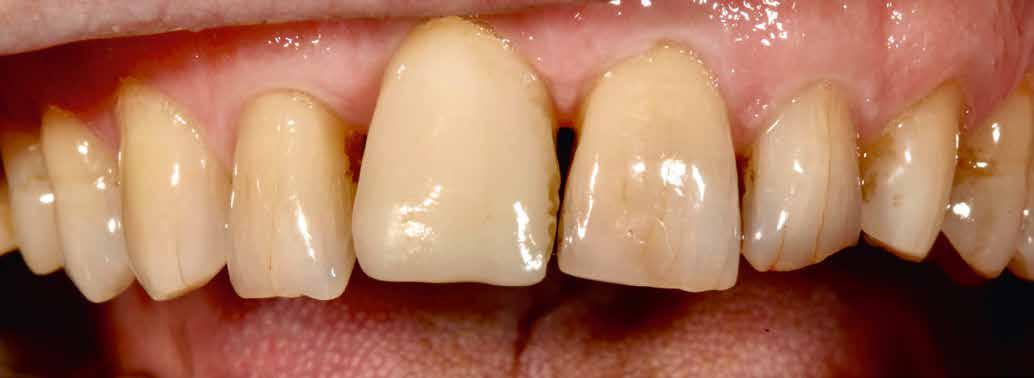

Elhagyott frontfogak, megtámadott parodoncium: a páciens kiindulási helyzete több mint nehéznek bizonyult. Yuki Momma és dr. William C. Heggerick, szerzőink, bemutatják, hogyan állítható helyre a harmónia a négy frontfog ellátásával.

A felső frontfogak állapota elhanyagolt, a parodontális struktúrák részben erősen károsodottak, VMK korona az 12 zónában, az ínyszél szürke, fekete approximális háromszögek… vörös-fehér esztétikáról nem is beszélhetünk (1. kép). Így jelentkezett a hölgypáciens a Weston Dental Specialists Group rendelőben. Elvárásai magasak voltak. A defektusok kezelését, a gingiva lefutásának korrigálását kívánta. Gyorsan világossá vált, hogy a megoldást csak a négy frontfog teljes kerámiakoronával való ellátása jelentheti. A jelen eset bemutatja, hogy az IPS e.max ZirCAD Prime segítségével hogyan lehet tiszta, tetszetős és esztétikus mosolyt létrehozni.

1. kép: Kiindulási helyzet.

A kialakítás tervezése

A páciens aggodalmas volt, hogy ne kapjon túl nagy és szögletes koronákat. A vele folytatott megbeszélések során viaszmintázat, majd annak alapján kulcs készült a mock-uphoz. Ennek segítségével az újonnan készülő pótlás formáját közösen, egyértelműen határozhattuk meg (2. kép).